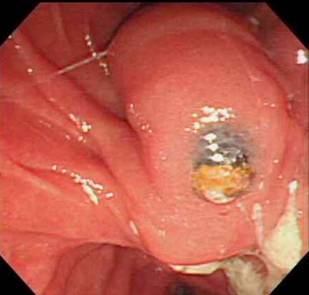

주로 돌이나 종양 때문에 담관이 막혀 염증이 발생하는데 담관염이 확인되면 먼저 응급으로 내시경을 이용하여 (ERCP) 쓸개즙을 배농시켜야하며 때에 따라서 막힌 부위를 뚫어 주어야합니다.

현재 각종 담관 및 췌장 질환의 진단과 치료에 있어 내시경 시술이 필수적이며 실제로 담관 결석과 담석에 의한 췌장염의 치료는 대부분 내시경으로 치료를 하고 있다.

첫째는 특수 제작된 내시경(십이지장경)을 식도, 위를 거쳐서 십이지장 제 2부까지 유치시키고, 췌-담관이 십이지장으로 개구되는 유두부를 찾아서 육안으로 관찰하고, 카테터(가느다란 관)를 내시경 내의 작업관을 통해 췌관 혹은 담관으로 삽관한다.

둘째는 삽관된 카테터로 방사선 조영제를 주입하여 담관 또는 췌관에 대해 방사선 투시 및 촬영을 하여 진단을 하고 필요하면 유두부를 절개하여 담관-췌관의 병을 치료하는 것이다. 이런 시술을 내시경 역행성 담도-췌관 조영술(ERCP)이라고 한다. 즉, 이 검사는 내시경 검사와 방사선 검사 둘 다를 포함한다. 따라서 ERCP를 시술하는 의사는 내시경 술기와 투시 조영술 모두에 전문가이어야 한다. 또한 ERCP를 이용한 중재적 시술은 상부소화관내시경 검사보다 시간이 더 걸리고 중증의 합병증 위험이 있어서 모든 내시경의사가 ERCP를 할 수는 없고 전문적인 수련 과정을 이수한 후에 시술을 하는 것이 바람직하다.